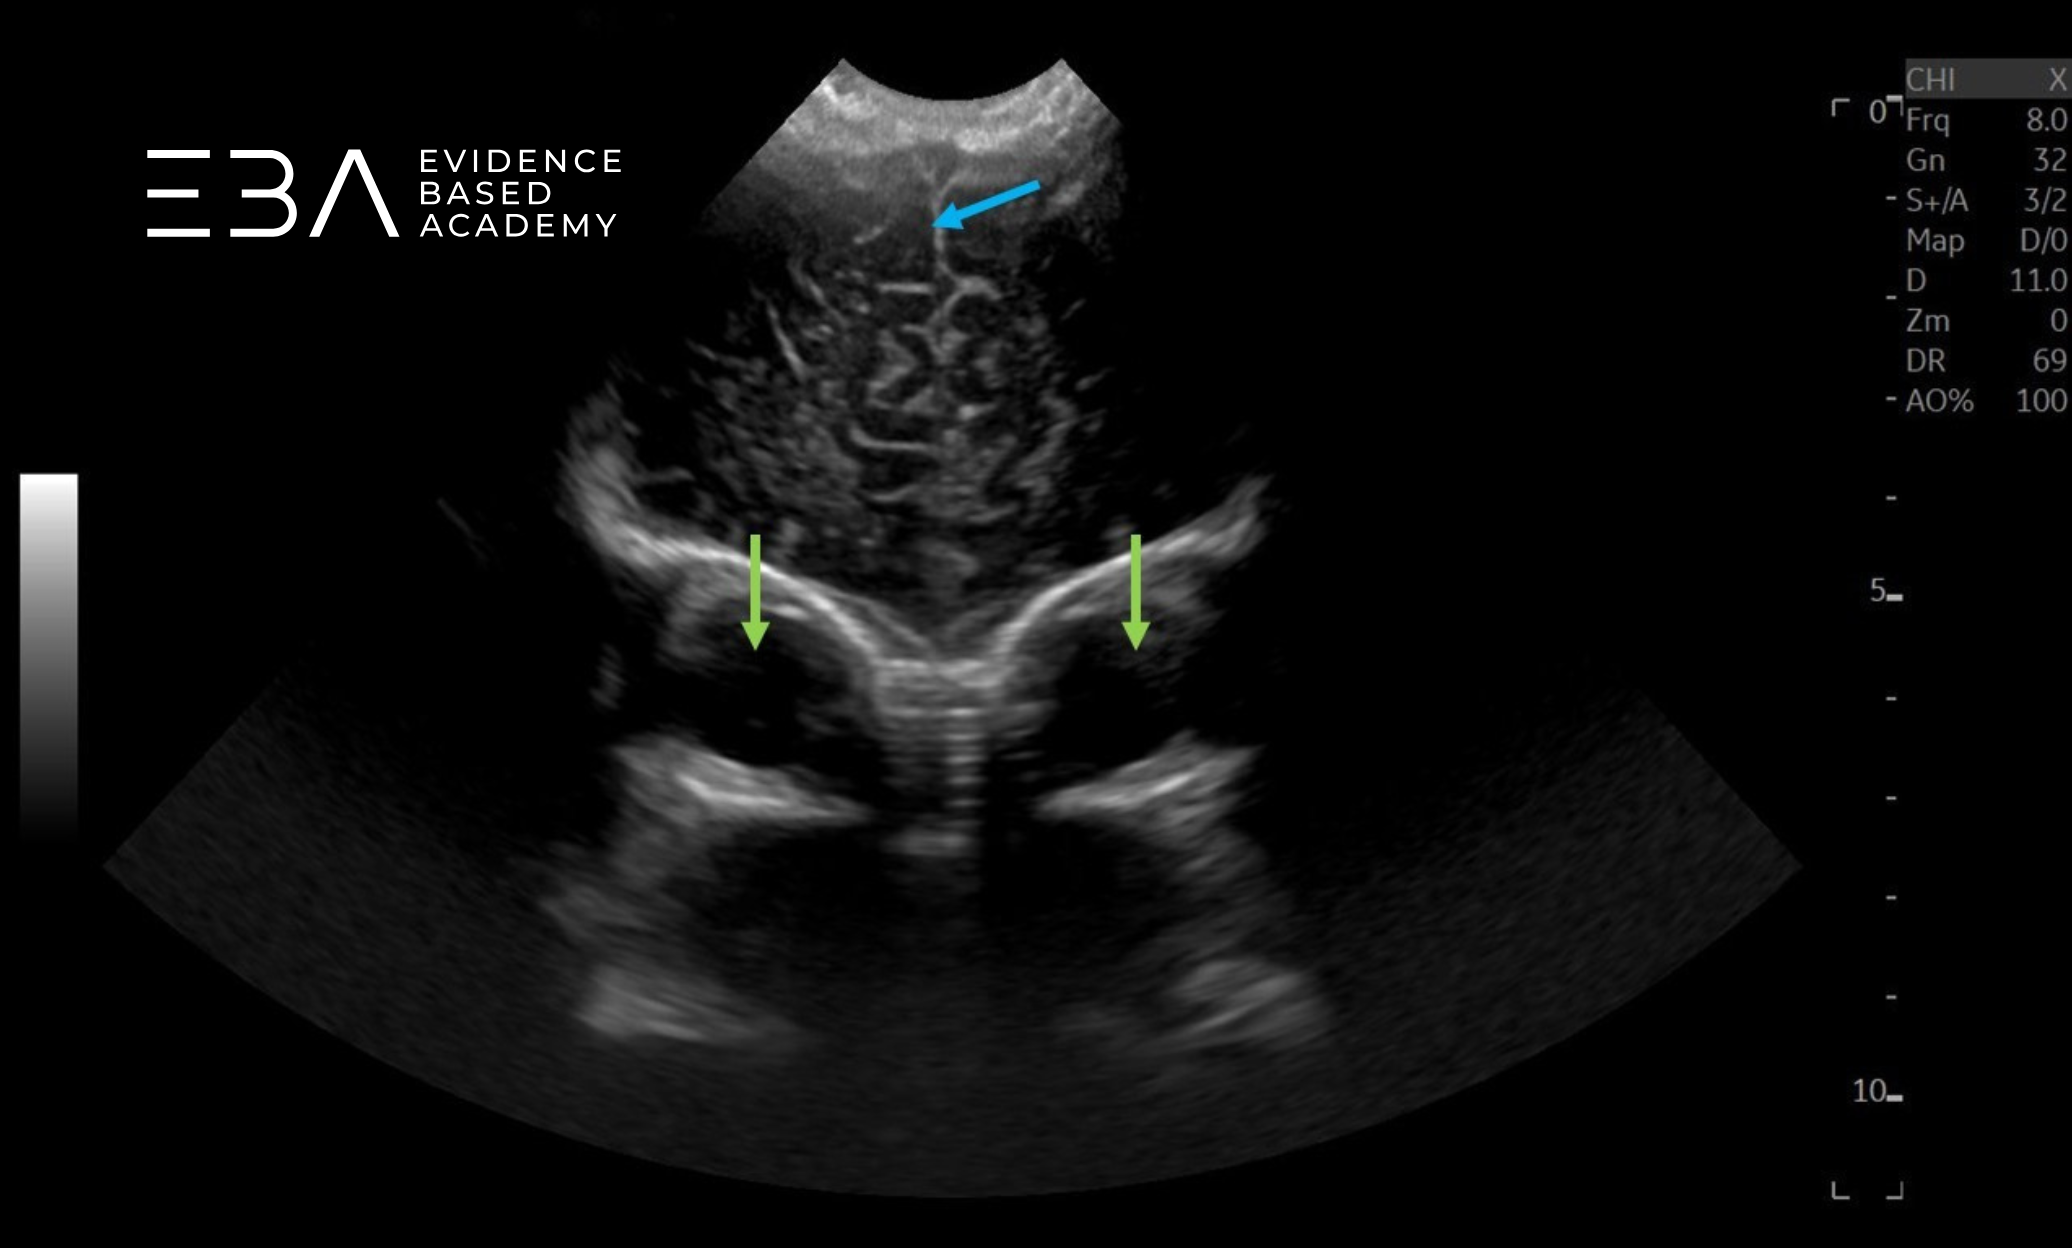

zdj. 0

Głowica sektorowa. Strzałkami zaznaczono półkule móżdżku. Słaba jakość obrazu struktur położonych blisko głowicy.